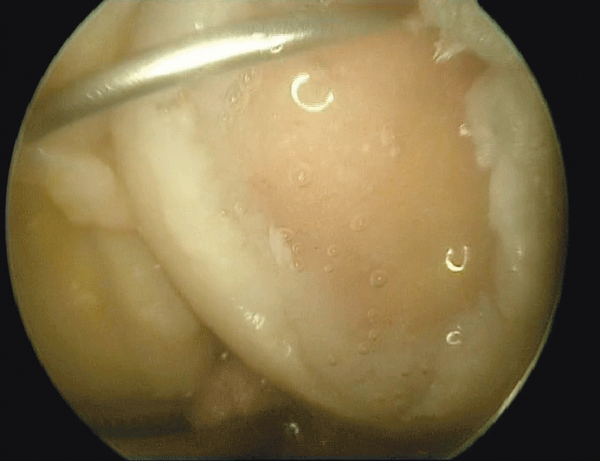

Bei der Osteochondrosis dissecans ermöglicht die MRT (links) die exakte Lokalisation, Verlaufskontrolle und Einschätzung der Vitalität. Eine genauere Beurteilung gelingt mittels Arthroskopie (rechts). Bei der Osteochondrosis dissecans ermöglicht die MRT (links) die exakte Lokalisation, Verlaufskontrolle und Einschätzung der Vitalität. Eine genauere Beurteilung gelingt mittels Arthroskopie (rechts). © Jerosch J. internistische praxis 2018; 59: 253-272; © Mediengruppe Oberfranken – Fachverlage GmbH & Co. KG, Kulmbach

Als wichtige Differenzialdiagnose der Arthrose bei jüngeren Patienten nennt der Experte die Osteochondrosis dissecans. Sie manifestiert sich meist gegen Ende des Wachstums, selten im Kindesalter oder jenseits des 50. Lebensjahres. Eine aseptische Nekrose im subchondralen Knochen führt dazu, dass der bedeckende Knorpel als freier Gelenkkörper („Gelenkmaus“) abgestoßen wird. Betroffene klagen v.a. über Belas­tungsschmerzen und Blockierungen.

Freie Gelenkkörper lassen sich nur selten tasten, sind aber im MRT lokalisierbar. Patienten mit stabilem Dissektat werden bis zum Abschluss des Wachstums konservativ behandelt. Eine absolute OP-Indikation stellt die Ablösung oder Instabilität des Dissektats dar, auch eine knorpelchirurgische Therapie ist möglich.